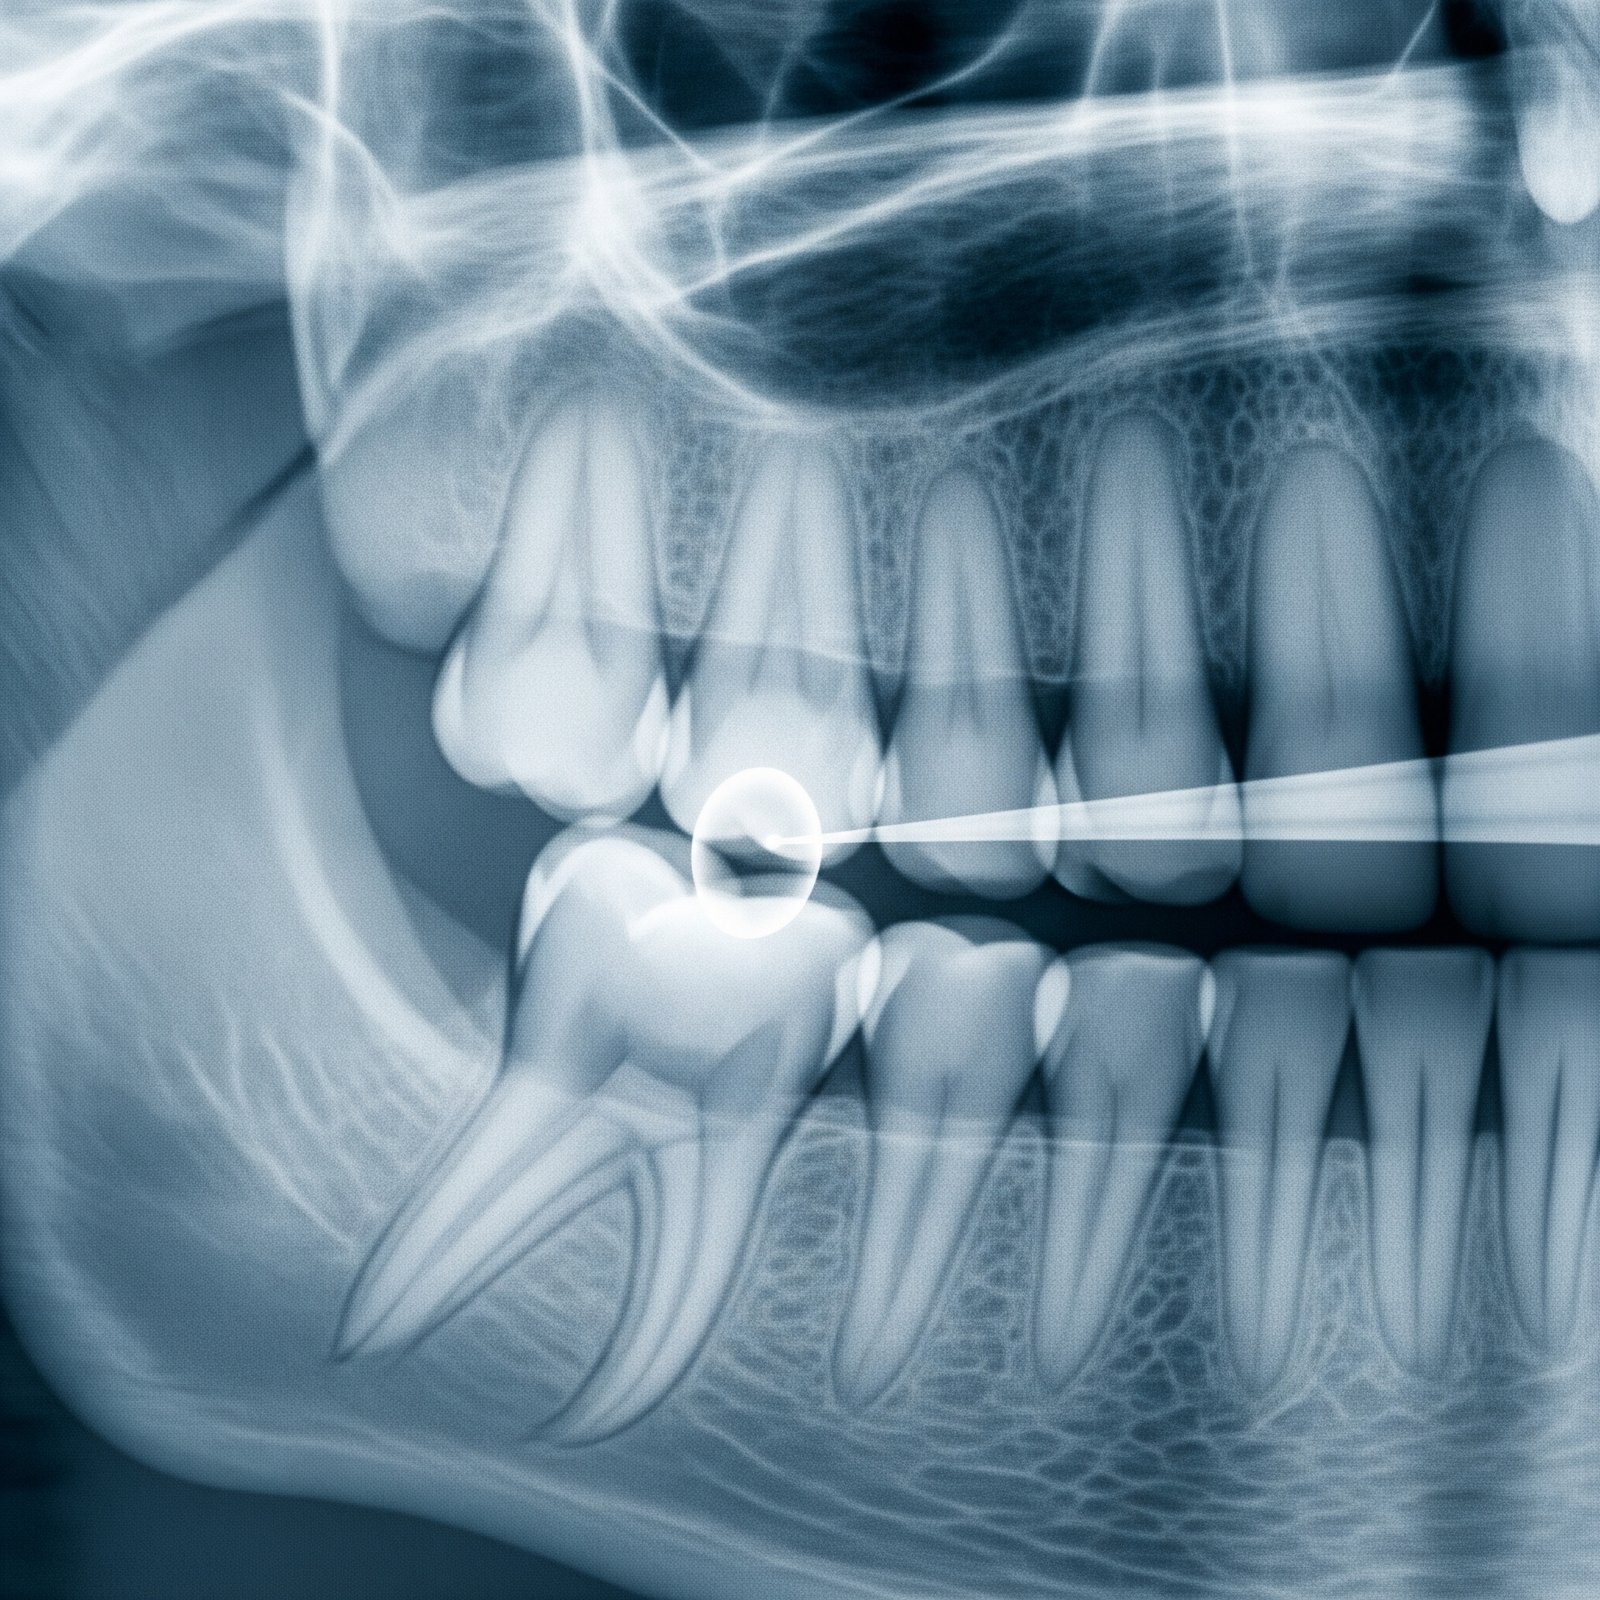

Paslaugos Dantų implantacija All - on - 4(žandikaulio aktūrimas ant keturių implantų) Chirurginės burnos intervencijos Dantų protezavimas Profesionali burnos higiena Dantų balinimas Terapinis gydymas, dantų plombavimas Vaikų dantų gydymas Estetinis plombavimas Endotontija Rentgenologiniai tyrimai